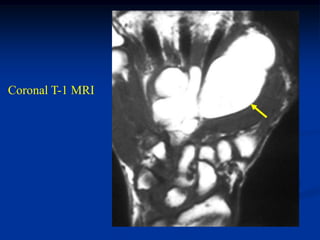

74 year female with intramuscular lipoma hand

Coronal T-1 MRI

Axial T-1 MRI